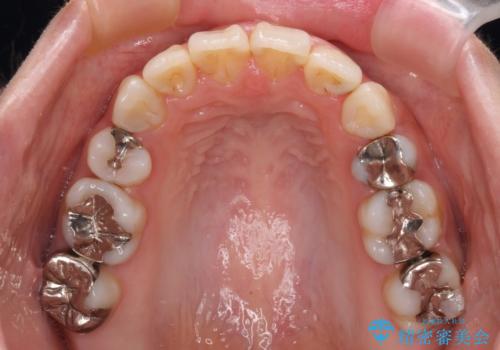

- 口元の突出感と奥歯の欠損を気にして来院された患者様です。

口元の突出感改善には、上下左右の第一小臼歯4本を抜歯し、奥歯の欠損部には矯正治療の途中でインプランを埋入していくこととしました。

矯正治療の後半にインプラント埋入を行うことで、トータルの治療期間を短縮することができました。